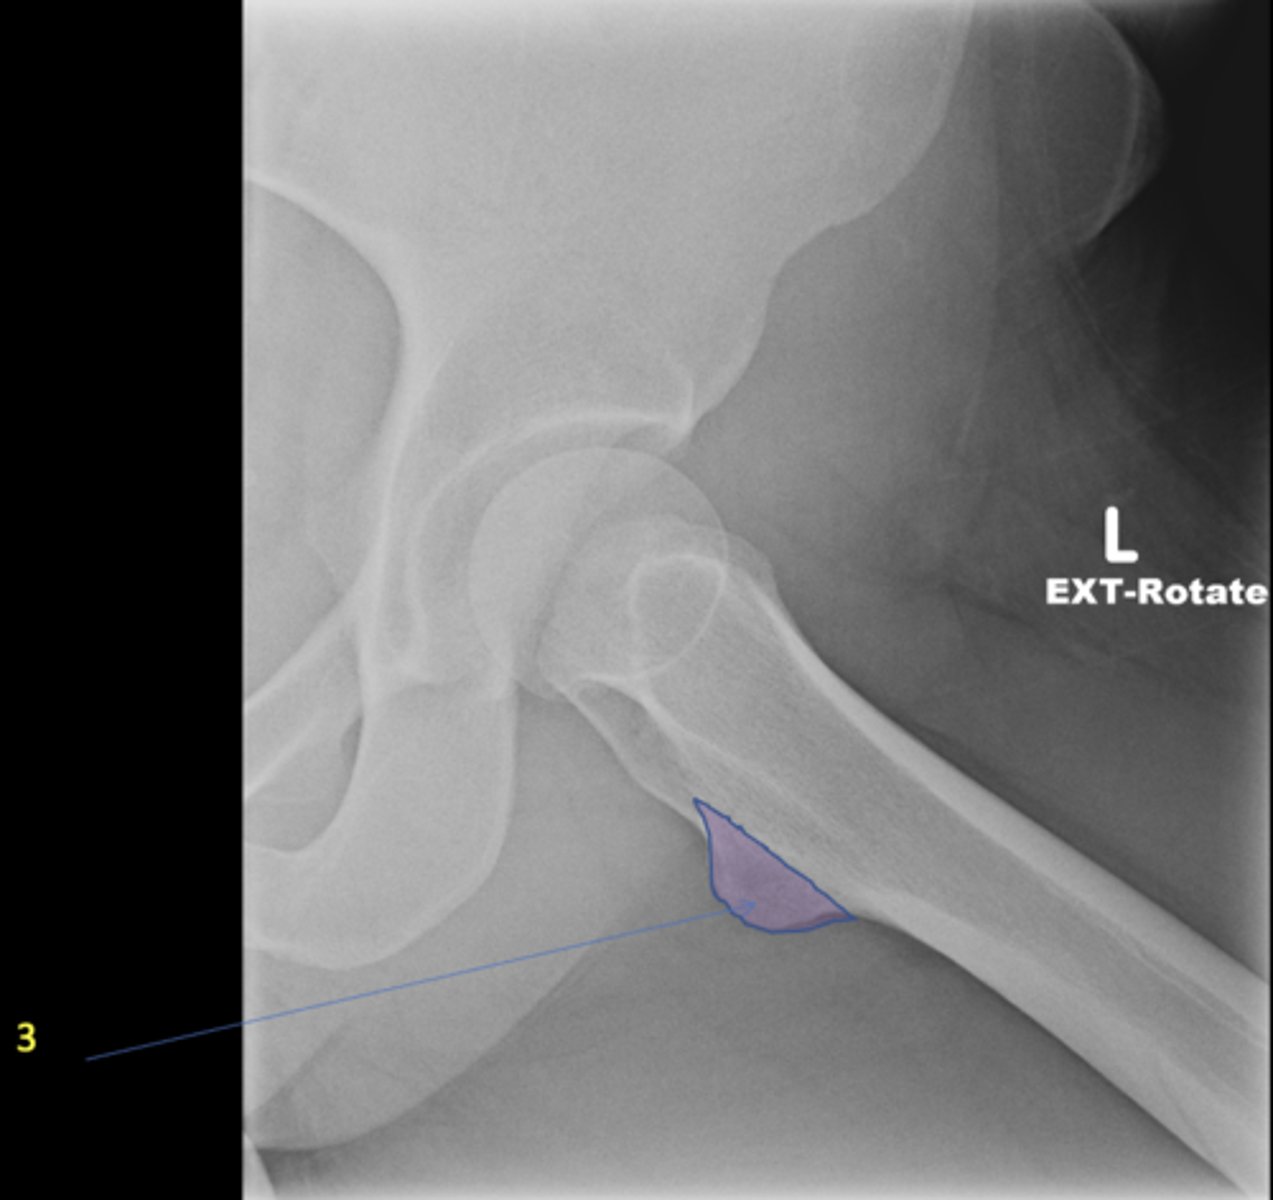

Left frog-leg hip

View?

<p>View?</p>

45

New cards

Lesser trochanter

ID 3

<p>ID 3</p>